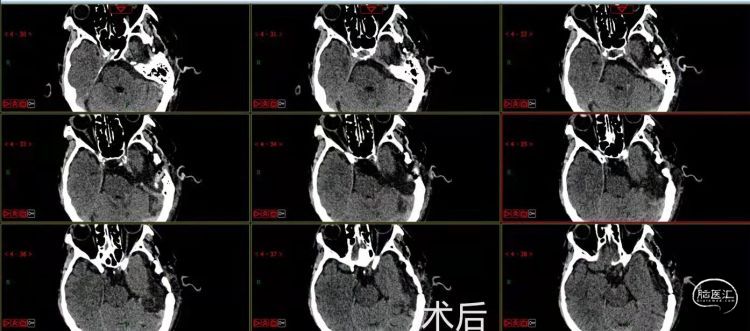

手术顺利,患者目前恢复良好,病情平稳,未诉疼痛。

该患者肿瘤分布于桥小脑角、脚间池、鞍上池,分布范围广、手术难度大。